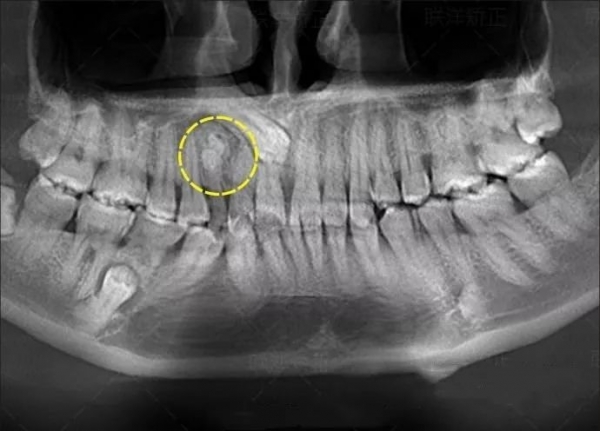

患者是30多歲的年輕男子,紅色標(biāo)記那顆牙松動,要求拔牙,開始嫌麻煩不愿拍片,后來經(jīng)過再三勸說還是拍了片。結(jié)果把所有人包括他自己都嚇了一跳。估計是良性,具體還得去醫(yī)院住院手術(shù)做病理檢查,所以大家不要忽視一張片子帶來輔助檢查的重要性。

試想,如果沒有拍片,直接貿(mào)然拔牙,一旦出現(xiàn)問題......一張牙片,“救”了診所,也救了患者!牙齒的硬度比骨骼還高,僅靠肉眼檢查是無法得知牙齒內(nèi)部情況的。

因此,如果牙齒出了問題,齒科醫(yī)生就需要有“透視”功能的X線片來檢查。通過x線片不僅能了解牙齒本身的病變情況,還可以了解牙根下有沒有囊腫、周圍骨頭有沒有吸收以及牙槽骨內(nèi)是否有埋伏牙、多生牙等。依據(jù)X線片綜合分析,可以提高齒科醫(yī)生診斷治療牙齒的準(zhǔn)確性和成功率。常見的牙科放射檢查包括曲面體層片( 全景片 )、小牙片、頭顱正側(cè)位片、全頭顱 CT、錐形束 CT( CBCT )等。由于牙齒下部隱藏在牙槽骨中,口腔醫(yī)生要了解牙齒的整體情況就需要拍攝全景片;要了解個別牙根及周圍變化,則選擇拍攝小牙片。醫(yī)生要判斷牙槽骨是否符合種植條件,或者了解埋伏阻生齒的三維位置以及其他頜骨內(nèi)病變組織的形態(tài)大小時,則需要進(jìn)一步拍攝 CBCT 。所以,拍牙片是一種幫助齒科醫(yī)生進(jìn)行診斷、治療、療效評估的重要手段,治療前用于發(fā)現(xiàn)病變程度、范圍;治療中用于引導(dǎo)治療、確定治療范圍和深度;治療后用于觀察療效。輻射分為電離輻射(如X光)和非電離輻射(如手機(jī)、微波爐),這里主要講述的是電離輻射。電離輻射的測量單位是西弗(Sv),但西弗是個非常大的單位,因此通常使用毫西弗(mSv)和微西弗(μSv),1Sv=1000mSv,1mSv=1000μSv)根據(jù)國際放射防護(hù)委員會(IRPA)提供的信息,每人每年受到的輻射劑量大約在2.5毫西弗左右,這個數(shù)值受地域緯度的影響而波動。其中大約80%來源于自然界,20%來源于人工輻射。而拍牙片是什么樣的輻射水平呢?根尖片為 5.2 μSv ,全口根尖片為 72.32 μSv ,曲面體層片為 10 ~ 23 μSv ,頭顱正位片為 1 ~ 5 μSv ,頭顱側(cè)位片為 1 ~ 3 μSv ,讓人「聞風(fēng)喪膽」的 CBCT 劑量一般也在 300 μSV 之內(nèi)。為了幫助大家更容易理解,我們用單位面積內(nèi)的香蕉數(shù)量表達(dá)輻射強(qiáng)度。之所以選擇香蕉,是因為香蕉富含鉀元素,天然鉀當(dāng)中約有0.0117%的放射性鉀——鉀40,而鉀40的半衰期長達(dá)12億5千萬年(地球歲數(shù)大約45億年)。